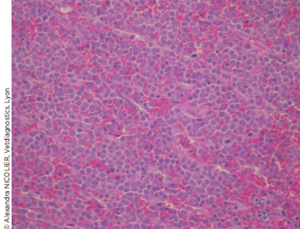

L’analyse histopathologique conclut à un lymphome splénique diffus de haut grade. Le parenchyme splénique est sévèrement infiltré par une prolifération densément cellulaire de plages de cellules rondes à cytoplasme peu abondant et à noyau rond fortement nucléolé.

Quelques cellules montrent une multinucléation. Les mitoses sont fréquentes (12/ champs x 400) et l’anisocytose et l’anisocaryose sont marquées (Photo 5).

Photo 5. Vue microscopique (HE, grossissement x 40) d’une coupe histologique de la rate. Le parenchyme est sévèrement infiltré par une prolifération densément cellulaire de plages de cellules rondes à cytoplasme peu abondant. Les mitoses sont fréquentes et l’anisocytose et l’anisocaryose sont marquée.

Le stroma contient de multiples petits amas de petits lymphocytes matures.